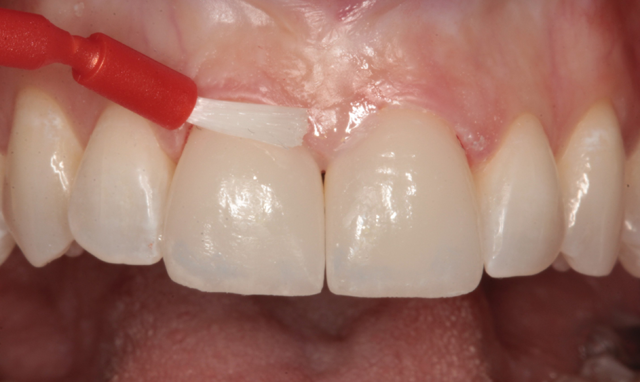

Celluloid strips were placed distal to both central incisors to protect the adjacent teeth. Phosphoric acid edging gel (Calibra, Dentsply/Sirona) was placed on the prepared enamel surfaces (Fig. 10), thoroughly rinsed after ten seconds (Fig. 11) and air dried (Fig. 12).

Fig. 11 Fig. 12